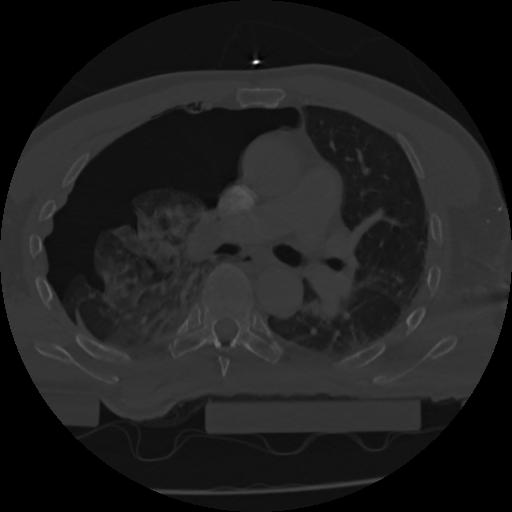

22 ANGIO,CE,Vol,0.5,ANGIO,,